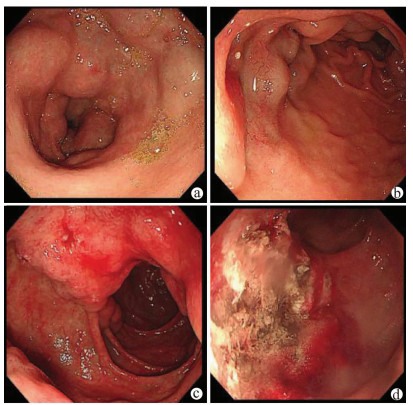

Value of SpyGlass single-operator choledochoscopy system in the diagnosis and treatment of patients with biliary tract diseases

Si ZHAO, Xueru WU, Linlin YIN, Lin MIAO, Guozhong JI, Xiuhua ZHANG

2021, 37(10): 2395-2399. DOI: 10.3969/j.issn.1001-5256.2021.10.027

Abstract(2421) HTML (611) PDF (2327KB)(107)

Abstract:

Objective  To investigate the value of SpyGlass single-operator choledochoscopy system in the diagnosis and treatment of patients with unexplained biliary stricture, complex bile duct stones, or other biliary tract diseases.  Methods  A retrospective analysis was performed for the clinical data of the patients with biliary tract diseases who were diagnosed and treated with SpyGlass in The Second Affiliated Hospital of Nanjing Medical University from December 2017 to June 2020. For the patients with biliary stricture, the biliary lesions were fully visualized under the guidance of SpyGlass, and SpyBite biopsy was performed if necessary; the patients with bile duct stones were treated with SpyGlass-guided direct-view laser lithotripsy; for the patients with gallbladder disease, the cystic duct was superselected with the assistance of SpyGlass. The SpyGlass system was analyzed in terms of its sensitivity, specificity, and accuracy rate in diagnosis and treatment, lithotripsy success rate, stone clearance rate, procedure success rate, and incidence rate of complications.  Results  A total of 58 patients underwent SpyGlass procedure. SpyGlass was used to evaluate biliary stricture of unknown nature in 44 (76%) patients; SpyGlass visual impression had a diagnostic sensitivity of 92% (24/26), a specificity of 94% (17/18), and an accuracy of 93% (41/44), and SpyBite biopsy had a diagnostic sensitivity of 71% (15/21), a specificity of 92% (11/12), and an accuracy of 79% (26/33). SpyGlass was used for the treatment of bile duct stones in 8 patients (14%), with a lithotripsy success rate of 83% (5/6) and a stone clearance rate of 88% (7/8). A guide wire under the SpyGlass system was to superselect the cystic duct in 5 patients (9%), with a procedure success rate of 80% (4/5). In one patient (1%), SpyGlass was used to assist the removal of common bile duct stones after liver transplantation and the treatment of bile duct anastomotic stricture. A total of 5 patients (9%) experienced complications after surgery.  Conclusion  The SpyGlass choledochoscopy system is accurate, safe, and effective in the diagnosis and treatment of unexplained biliary stricture, complex bile duct stones, and other biliary tract diseases.